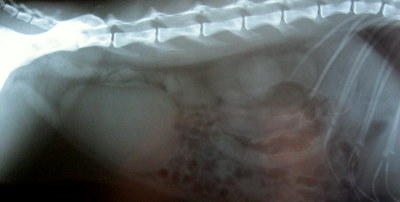

Op 1 maart 2011 wordt de 8 jaar oude zwarte poes Luca op de praktijk aangeboden tijdens het spreekuur. Ze heeft voornamelijk als klacht dat zij pijnlijk is bij oppakken en ze heeft één keer gebraakt. Bij het klinisch onderzoek wordt als enige afwijking een pijnlijke buik gevonden. Er wordt een röntgenfoto van de buik van Luca gemaakt en daarop zien we met name vóór in de buik een onrustig röntgenbeeld . Op basis van de zeer pijnlijke buik én de afwijkende röntgenfoto wordt besloten om in de buik van Luca te kijken (de zgn. proeflaparotomie) om te zien wat de pijnlijkheid veroorzaakt.

Het onrustige beeld op de röntgenfoto